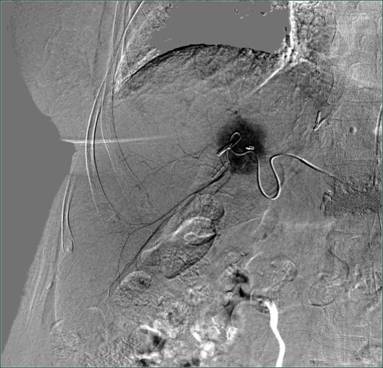

栓塞后图片: